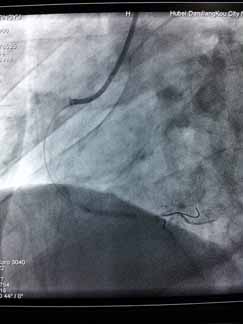

近日,烈日炎炎,急性心肌梗死高发,周六周日两天“120”急救车连续接诊两位急性心梗患者,到达我院后,心血管内科立即开通心梗绿色通道,最短时间内对两例病人实施急诊PCI,配合药物、抽吸导管及冠脉支架治疗,手术进行的非常顺利。门球时间均在60分钟内,堵塞血管立即开通,置入心脏支架,病人获得了最大收益,避免了急性心梗的高死亡率及不良后遗症。